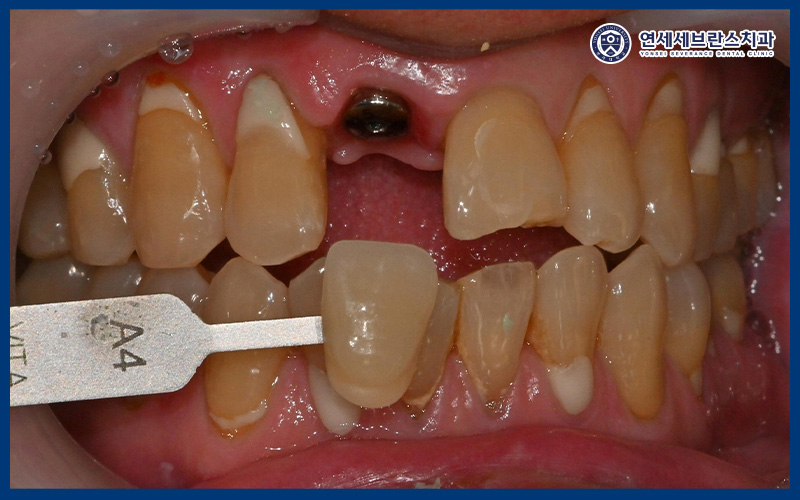

위 환자분께서는

내원 하루 전 넘어져서 앞니가 빠지고

흔들린다며 내원해 주셨습니다.

치아를 가능한 한 보존하는 치료를 원해

치과 보존과를 찾아오셨다고 해주셨습니다.

육안으로 확인 시 앞니가 부러져서

뿌리만 남아있던 상황이었습니다.

25.12.01

앞니는 심미적으로 중요한 부위이기 때문에,

치아의 형태와 색상뿐만 아니라

잇몸 라인과 주변 치아와의 조화를 고려하여

보철물을 제작하였습니다.